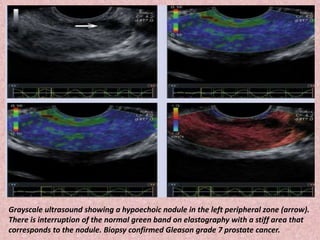

Grayscale ultrasound showing a hypoechoic nodule in the left peripheral zone (arrow).

There is interruption of the normal green band on elastography with a stiff area that

corresponds to the nodule. Biopsy confirmed Gleason grade 7 prostate cancer.

Grayscale ultrasound showinga hypoechoic nodule in the left peripheral zone (arrow). There is interruption of the normal green band on elastography with a stiff area that corresponds to the nodule. Biopsy confirmed Gleason grade 7 prostate cancer.